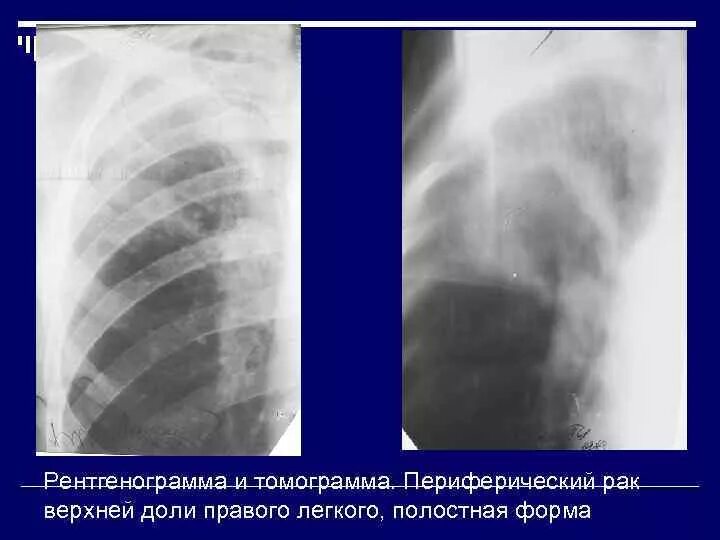

Образование в легком форму